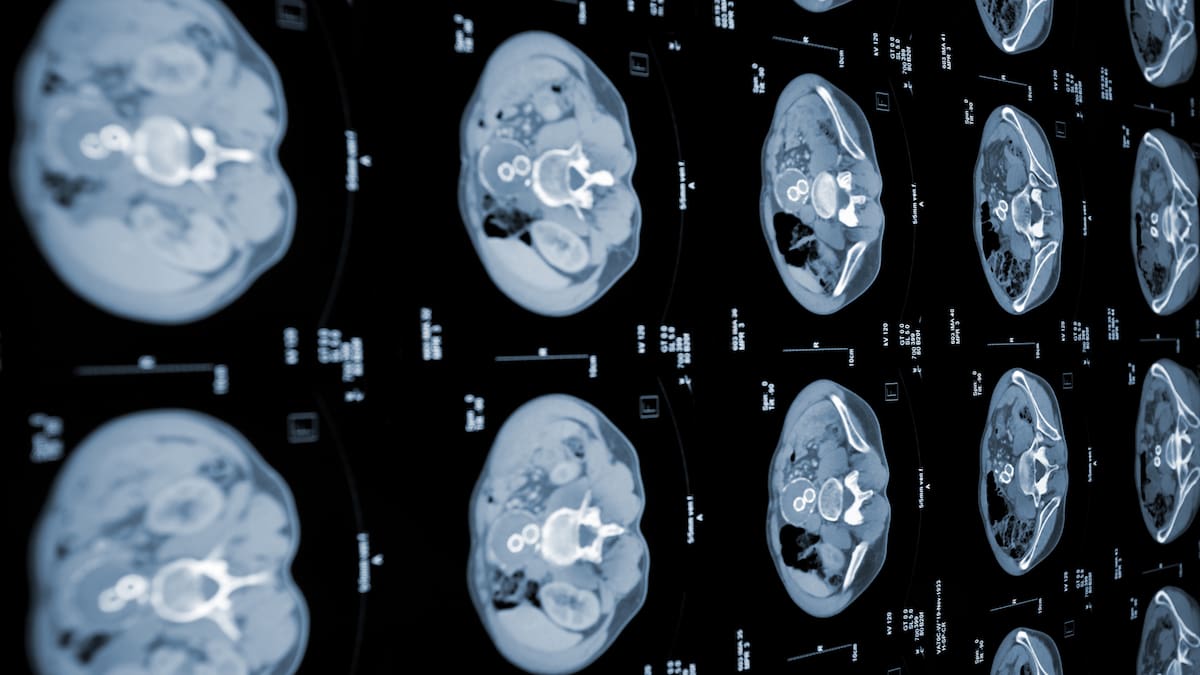

In China, the AI tool PANDA, developed by Alibaba's Damo Academy, is being used in hospitals to analyze routine CT scans and detect pancreatic cancer early, even without contrast. This has led to earlier interventions and saved lives, though it has also caused some false positives and unnecessary follow-ups.[AI generated]